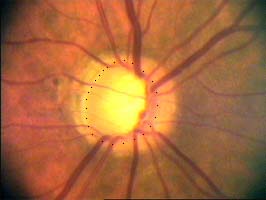

Na kterém oku je exkavace větší, na pravém nebo na levém? Podle pohledu na fotografie jistě na levém.

exkavace pravé oko

Na kterém oku je exkavace větší, na pravém nebo na levém? Podle pohledu na fotografie jistě na levém.

Co je příčinou toho, že při pohledu na snímky hodnotíme rozsah exkavace nesprávně? Je to skutečnost, že i růžová oblast neuroretinálního lemu může být již prohloubená, což vídáme zvláště na počátku rozvoje glaukomové neuropathie.

A jak se můžeme vyhnout záměně okrsku bledší barvy za skutečnou exkavaci? Tím, že budeme mít na paměti, že exkavace může být větší než nablednutí. Také zařazení zeleného filtru na pomůže snížit nežádoucí barevný kontrast.